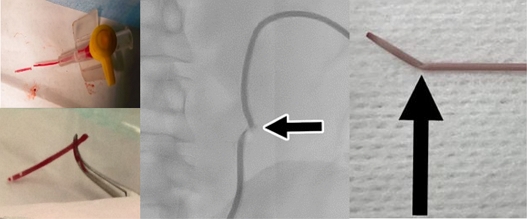

이 중 쉬스(Sheath)와 다일레이터(Dilator)는 술기 시작 단계에서 사용되는 카테터로서, 가이드 와이어(Guidewire) 혹은 진단치료용 최소 침습 의료기기를 경피적으로 진입해야 할 때, 천자부위 혈관의 손상을 방지하고 의료기기의 삽입 및 제거를 용이하게 도와주는 카테터이다[4].

최소 침습 시술을 위한 쉬스와 다일레이터 연계 경피적 진입방법은 Fig. 1에서와 같다. 천자침은 혈관을 천자한 후 가이드 와이어가 진입되기 위한 통로 역할을 하고, 가이드 와이어는 천자침 제거 후 쉬스와 다일레이터의 천자 부위 접근을 도와주며, 다일레이터는 피부에서 피하 조직을 통해 혈관으로 유로를 형성하여 경피적 진입을 유도하고, 쉬스는 진단 및 치료에 사용되는 카테터가 부드럽게 삽입되고 보호하는 역할을 하면서, 고정된 상태로 진단 및 치료가 끝날 때까지 유지한다. 특히 쉬스의 경우, 시술 시 지속적으로 삽입되어 혈관 내부로 삽입되는 다양한 카테터 등의 의료기기가 내벽의 손상 혹은 출혈없이 삽입될 수 있도록 유지해 주는 역할을 수행한다. 이와 같이 쉬스와 다일레이터는 카테터 삽입 시 자극으로 인한 혈관 벽의 상처 및 감염을 최소화하고, 안정적인 술기가 펼쳐질 수 있도록 유로를 확보해주는 최소 침습 기술의 필수적인 의료 기기이다[5].

Fig. 1

Procedure for using the introducer sheath & dilator